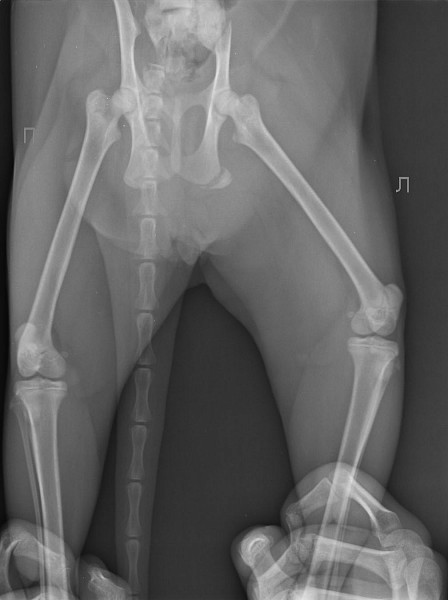

Перелом таза у собаки